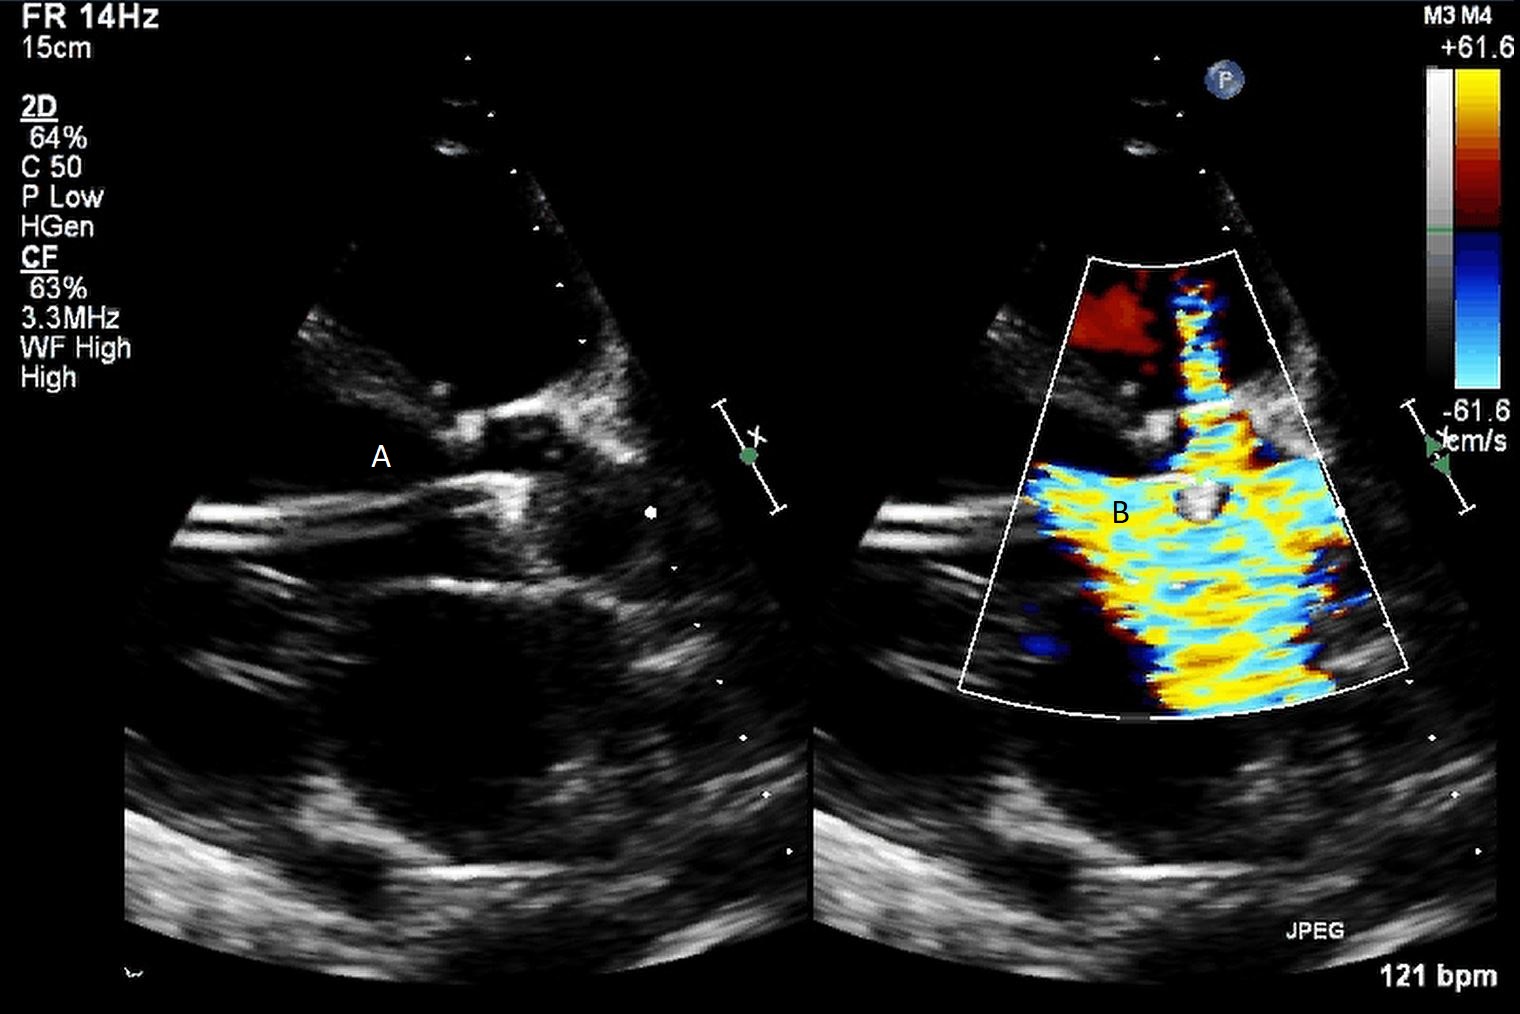

The intra-aortic balloon pump is a percutaneously placed counter pulsation device which helps in decreasing afterload as well as augmenting coronary perfusion. Initially developed in the 1960s it is the oldest MCS device and given its simplicity, cost effectiveness, and ease to implant and explant, it is the most commonly used temporary support device [6]. Although it is typically placed in the cardiac catheterization lab under fluoroscopic guidance, TEE can be utilized to help in its placement in the intubated patient in the intra-operative setting. The femoral artery is the most common site of placement however they can on occasion be placed in alternative sites such as the axillary artery or directly into the aorta [7, 8]. When placed via the femoral artery, it is threaded over a guidewire. TEE can be used to visualize both the guidewire as well as the tip of the IABP catheter during placement (Fig. 1) [9]. Ideal positioning of the balloon tip is 1–2 cm distal to the left subclavian artery to derive maximal hemodynamic benefit [10]. Positioning can be confirmed by visualizing the descending aorta and then withdrawing the TEE probe until the left subclavian artery and aortic arch are visualized. Upon activation of the balloon pump the gas filled balloon will cause shadowing and reverberation artifacts (Fig. 2). Its presence can be used as confirmation of proper function of the device. If these artifacts are not seen or bubbles are visualized in the aorta, rupture of the IABP should be suspected [9]. In addition to hemodynamic monitoring with a Swan-Ganz catheter, TTE can be used to monitor LV function after IABP placement and can help guide weaning of IABP support. It can also visualize any new or worsening aortic regurgitation. Given that IABPs work by reducing afterload, on rare occasions they can precipitate dynamic outflow tract obstruction and paradoxically worsen cardiogenic shock. Examples include patients with a relatively preserved basal or septal myocardial function in scenarios such as takotsubo cardiomyopathy or acute myocardial infarctions. Doppler imaging and color flow doppler can be used to identify such scenarios [11].

Fig. 1.TEE demonstrating IABP in descending aorta (A).

TEE demonstrating IABP in descending aorta (A) with reverberation artifact seen behind it upon activation (B).